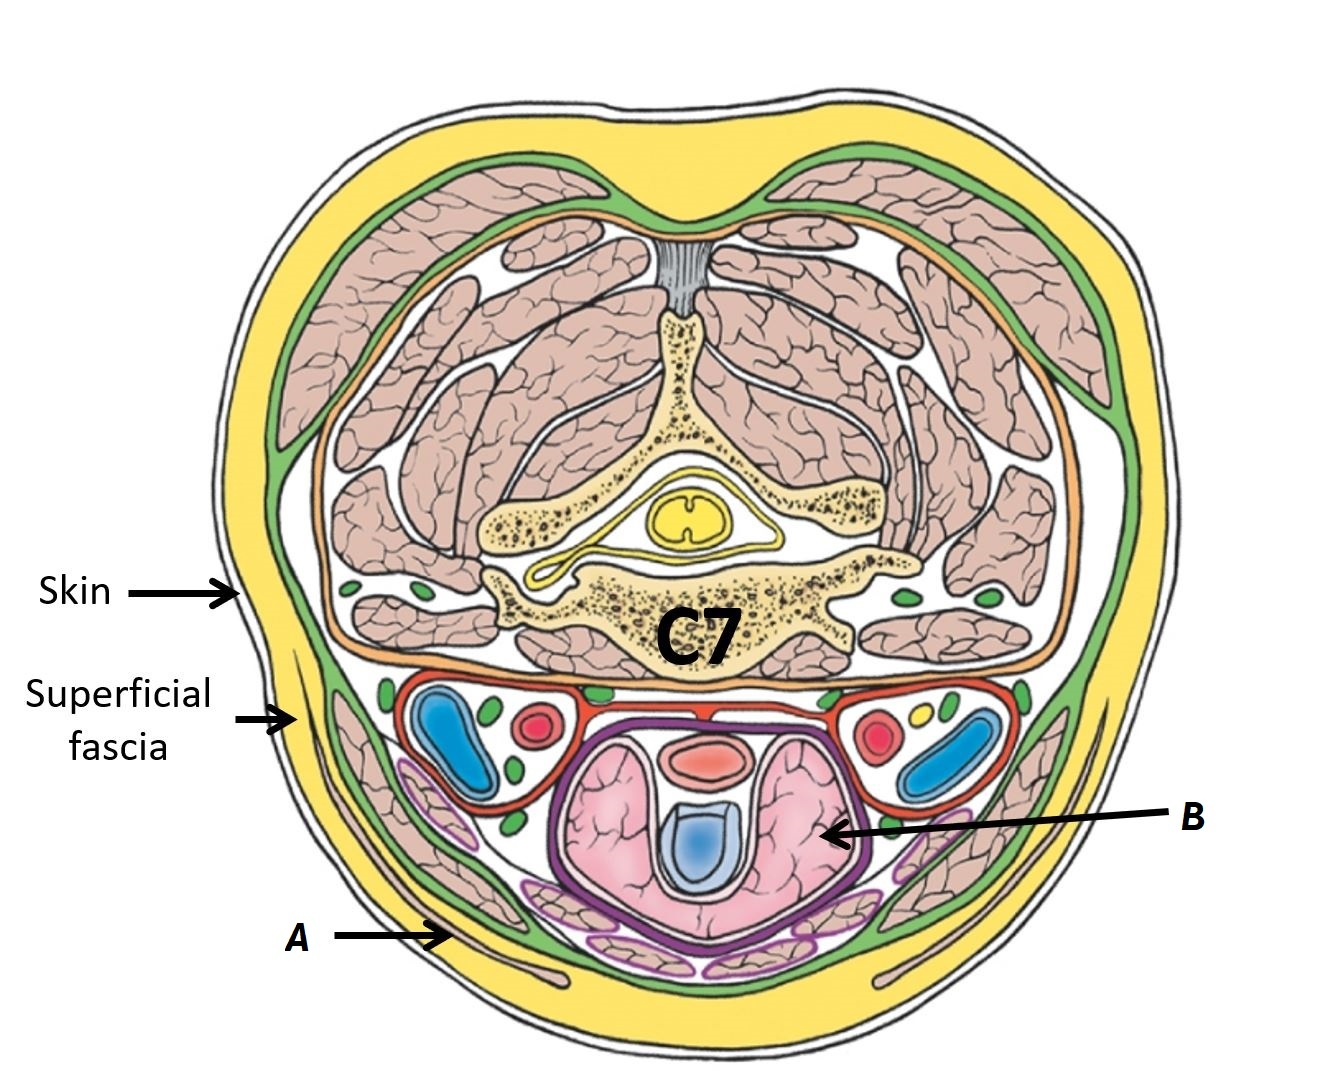

Name structures A to D

A - Strap muscles

B - Thyroid gland

C - Trachea

D - Oesophagus